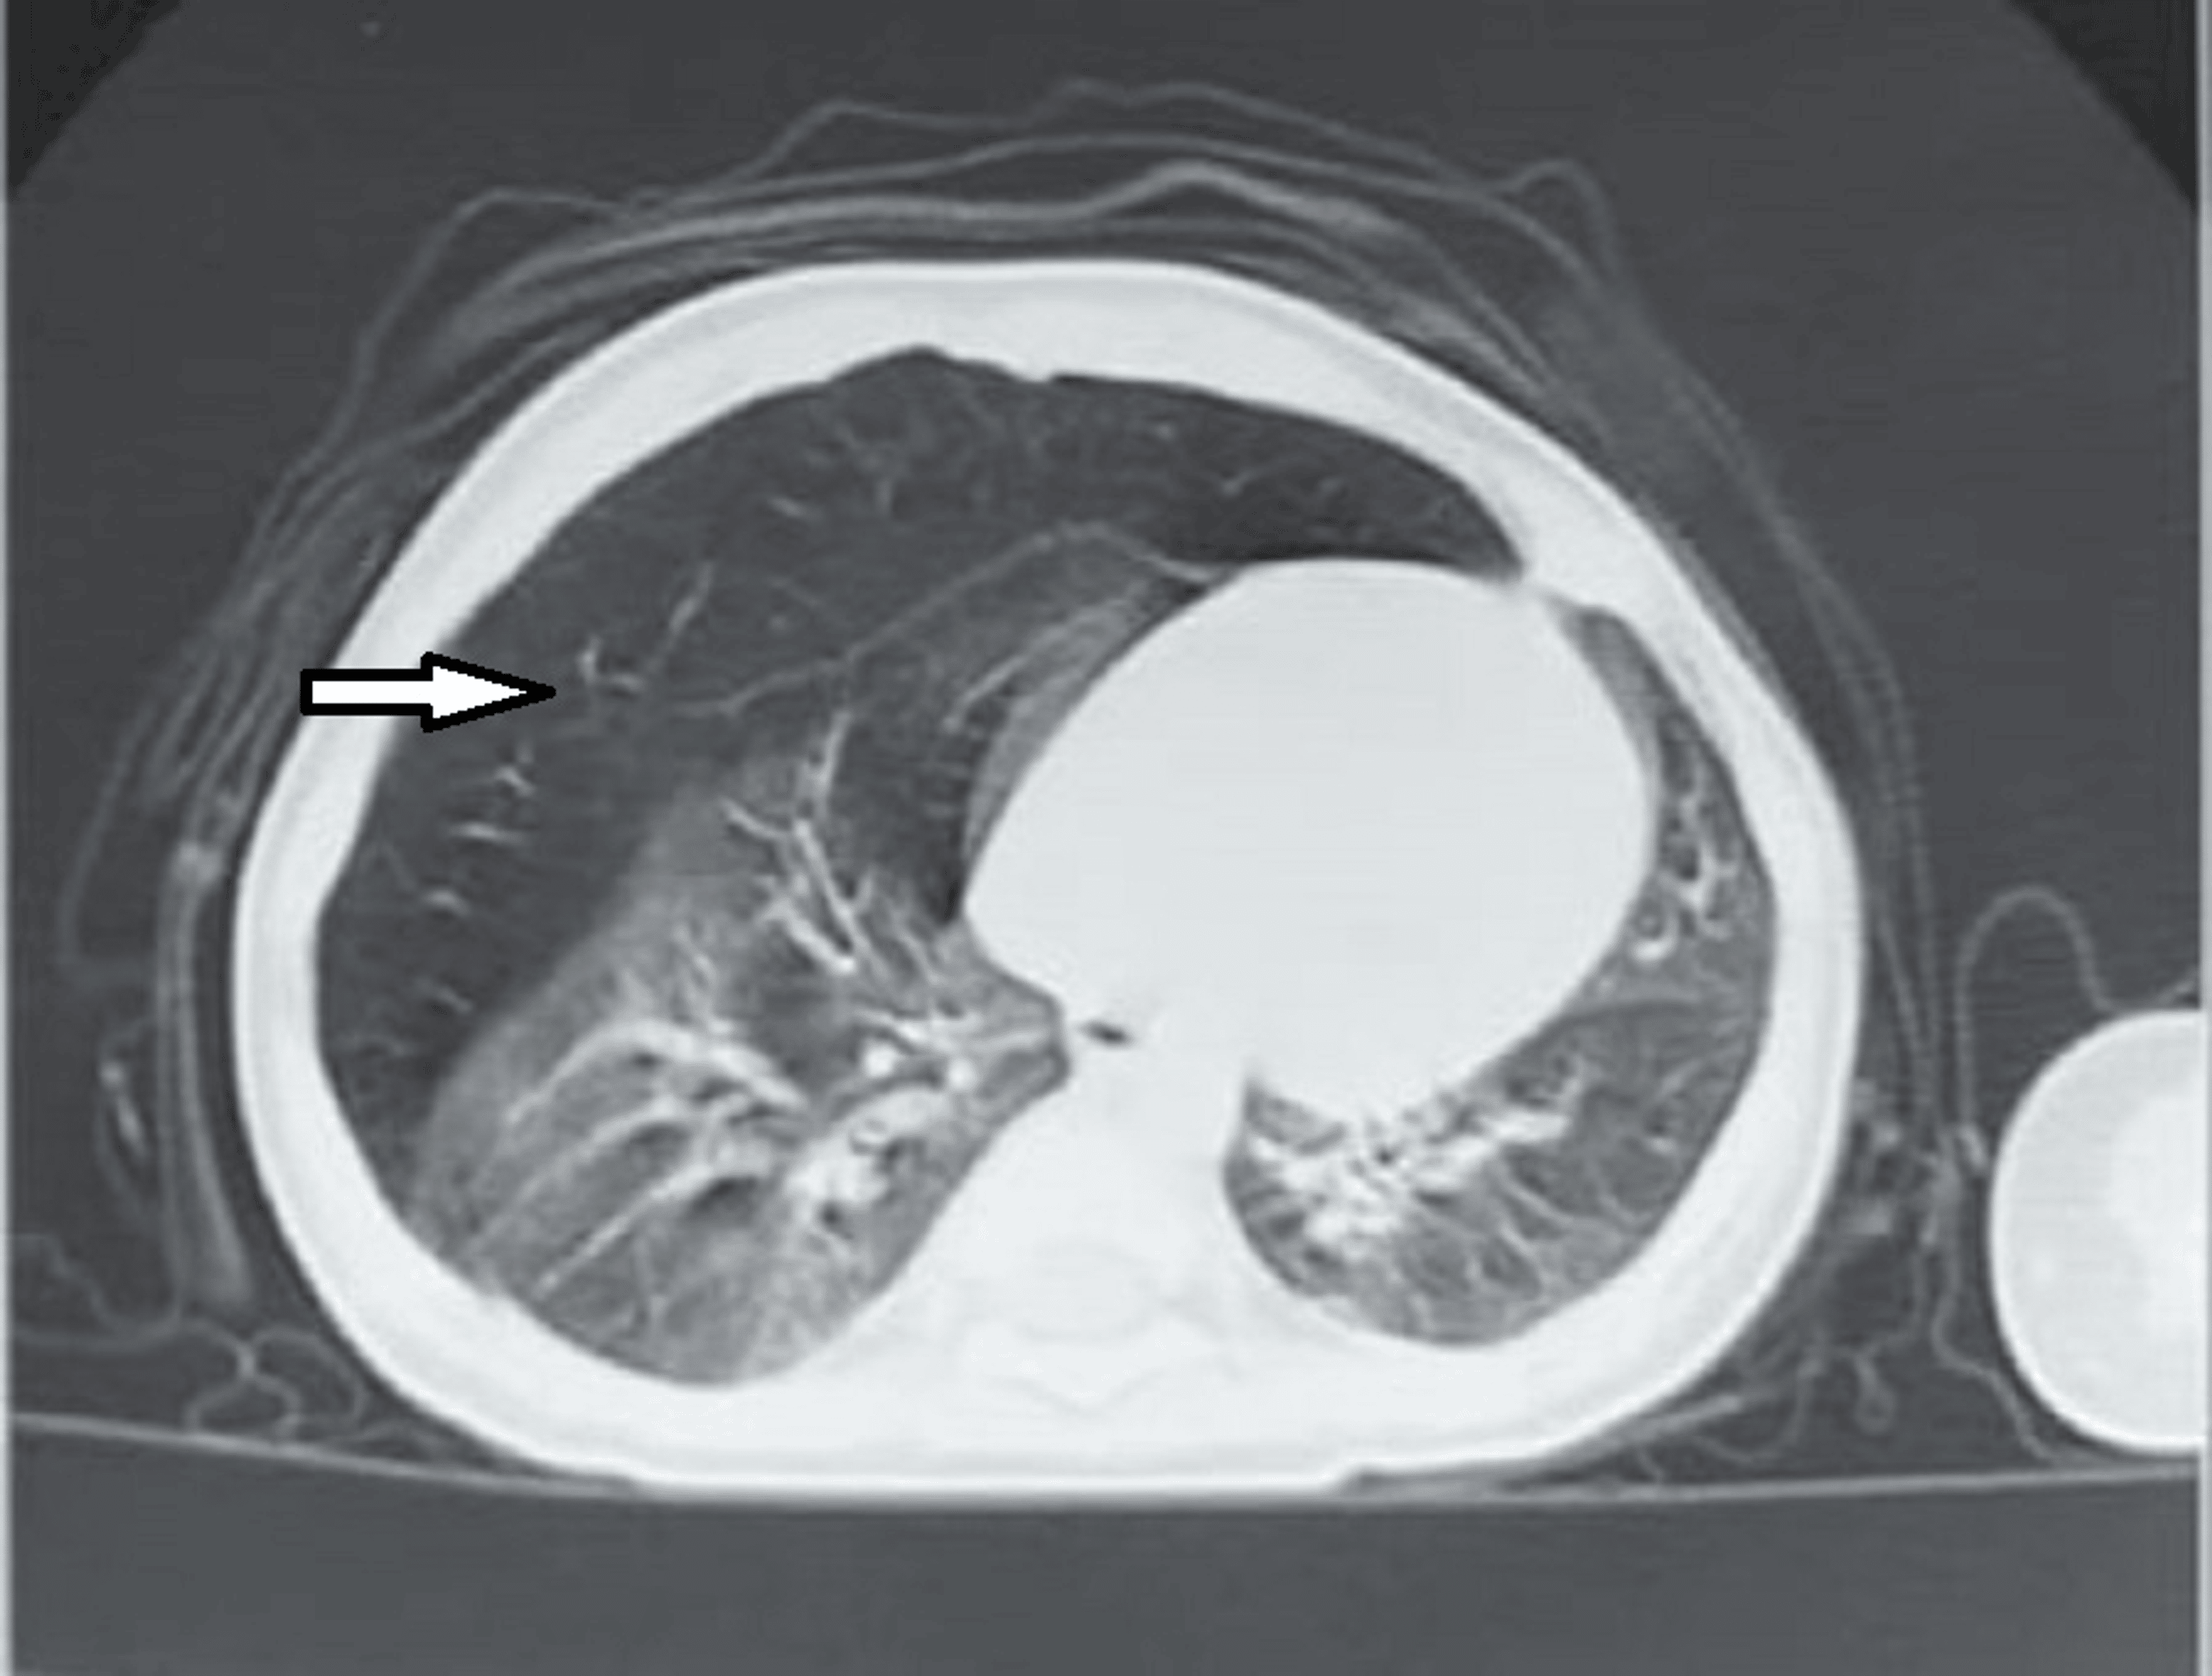

Radiology case Panlobular emphysema